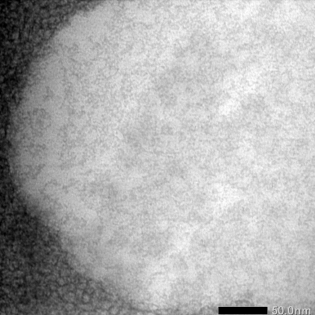

Characterization NLCs honey extract optimal formula with transmission electron microscopy (TEM)

TEM evaluation aims to look at microstructural analysis, defect identification, interface analysis, crystal structure, atomic arrangement in crystals, and nanometer-scale elemental analysis.

Fig. 6: TEM NLCs honey extract optimal formula. The magnifications are 40.000 x

Morphological tests are needed in NLC characterization, which aims to determine the shape and internal structure of NLC, which already contains active drug ingredients. Lipid crystals generally have a non-spherical platelet shape. The non-spherical shape of lipid nanoparticles has advantages, namely affecting NLC stability, entrapment efficiency (EE), drug loading, drug location in the NLC, and drug release rate, having a large surface area, short diffusion path, and low lipid layer compared to the non-spherical shape of lipid nanoparticles. Round requires more surfactant to stabilize the NLC [19]. This follows the NLCs of optimal formula honey with a high surfactant composition, namely 25.96. This morphology test can also determine the particle size of an NLC. The particle size determined by TEM was shown to be smaller than that determined by dynamic laser light scattering techniques. Based on observations, it was obtained that the NLCs of the optimal formula honey had separate particles, no lumps, oval shape, and smooth and uniform size, ranging from 100 nm to 200 nm. The optimal formula for honey NLCs was obtained using the high-pressure homogenization method.